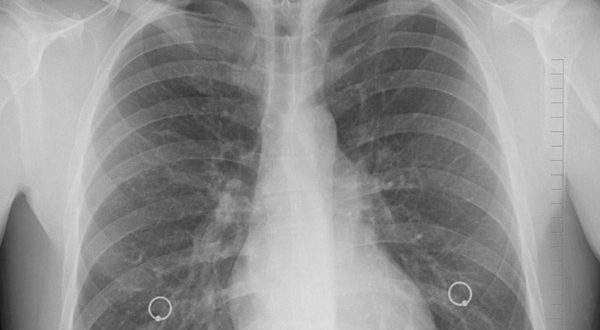

Mujeres son más propensas a padecer hipertensión arterial pulmonar

En México se han detectado alrededor de cuatro mil casos de hipertensión arterial pulmonar, enfermedad que afecta al corazón y los pulmones y cuyo blanco predilecto son las mujeres en etapa reproductiva.

La enfermedad, que no tiene cura y es catalogada como rara, pues se presenta en menos de cinco por cada 10 mil habitantes, se caracteriza por el aumento de la presión en las arterias pulmonares, aquellas que conectan los pulmones y el corazón.

Dichas arterias se vuelven más estrechas y hay menos espacio para que circule la sangre, lo que puede dar lugar, en los casos que no tienen diagnóstico y tratamiento oportuno, a una insuficiencia cardíaca que es una de las causas más frecuentes de muerte en este tipo de pacientes.